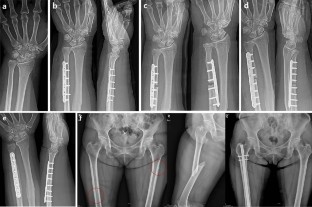

Five patients with histories of breast cancer and subsequent BP treatment were identified; all (100%) of these patients showed definitive nonunion after USO. The mean age was 56.2 years, and all ulnae were on the contralateral side to that of the original breast cancer. Intravenous Ibandronate® and Zolendronate® were administrated to one and four patients, respectively. The mean period of administration was 67.8 months. Three patients exhibited suspicious lesions impending atypical fracture on their femurs, and the other two patients were treated by intramedullary nailing after the occurrence of atypical fractures. Radiological evaluation revealed no evidence of a metastatic lesion, including in the musculoskeletal system, in any patient. Osteosynthesis was performed with cancellous iliac bone graft and mean of 4.3 months after osteosynthesis, union in all cases was achieved.

Fig. 1

Fig. 2